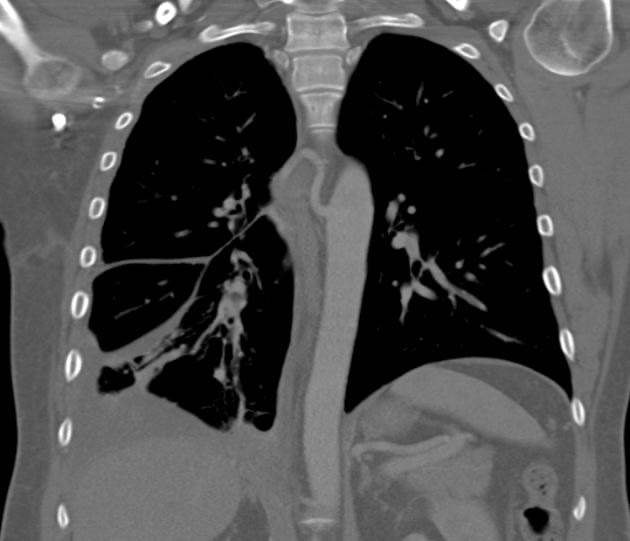

2895. Обнаруженные при компьютерной томографии признаки

у пациента, которого беспокоят частые эпизоды правосторонней пневмонии, наиболее характерны для